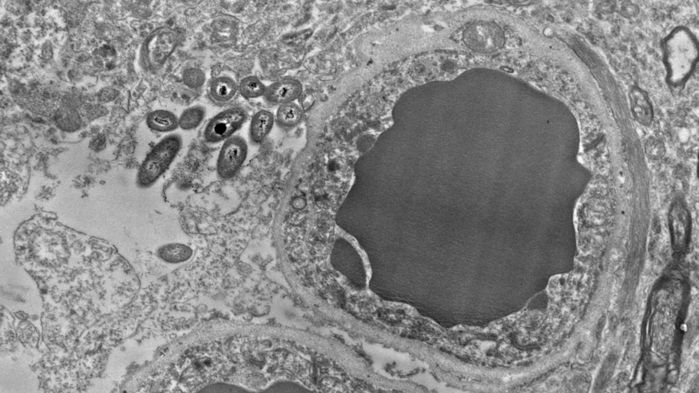

Nieoczekiwane odkrycie bakterii w mózgu sugeruje związek między mikrobami a mózgiem. Związek ten może być niezwykle podobny do związku mikroorganizmów z jelitami. Za to innowacyjne badanie odpowiada zespół dr Rosalindy Roberts, neuroanatoma z University of Alabama w Birmingham (UAB). Jej zespół bada różnice obserwowane do kilku godzin po śmierci w tkance mózgowej osób zdrowych i osób chorych na schizofrenię. Kilka lat temu neuronaukowiec Courtney Walker, będąca wówczas studentką w laboratorium Rosalindy Roberts, zafascynowała się niezidentyfikowanymi drobnymi elementami na fotografii elektronowej tkanki mózgu. Miały one kształt pręcików i pojawiały się w szczegółowych obrazach skrawków badanych pod mikroskopem elektronowym. Roberts zwróciła na nie uwagę wcześniej, ale nie wydały się jej interesujące. Walker była jednak wytrwała. Dr Roberts zaczęła więc kontaktować się z innymi badaczami z UAB, aby ustalić czym są owe obiekty. Nieoczekiwanie odpowiedź przyszła od bakteriologa – pojawiające się drobne elementy okazały się bakteriami. Zespół dr Roberts znalazł bakterie w każdym z 34 sprawdzonym mózgów, przy czym połowa z nich należała do osób zdrowych, a druga do osób ze schizofrenią.

Badanie przez zespół Roberts mikrografów elektronowych wykazało, że bakterie rezydujące w mózgu mają specyficzne preferencje. Wydaje się, że zamieszkują one komórki gwiaździste, tzw. astrocyty, które wspierają i oddziałują z neuronami. Bakterie skupiają się głównie wokół końców astrocytów, otaczając tym samym naczynia krwionośne przy barierze krew-mózg. Występują też bardziej obficie wzdłuż długich neuronów otoczonych mieliną. Może to świadczyć o preferowaniu przez te bakterie miejsc w komórkach mózgu bogatych w cukry i tłuszcze.